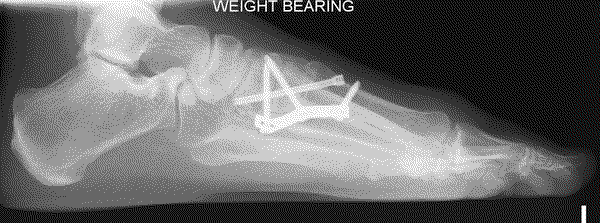

The severity of the condition is assessed by an X-ray. There is no direct correlation between the size of the deformity and the degree of symptoms experienced.

This involves a fusion of the first metatarsal cuneiform joint, allowing the first metatarsal to be rotated back into a straight position. It is normally reserved for severe deformities. Once the corrected position has been obtained it is usually maintained with a plate and screws.